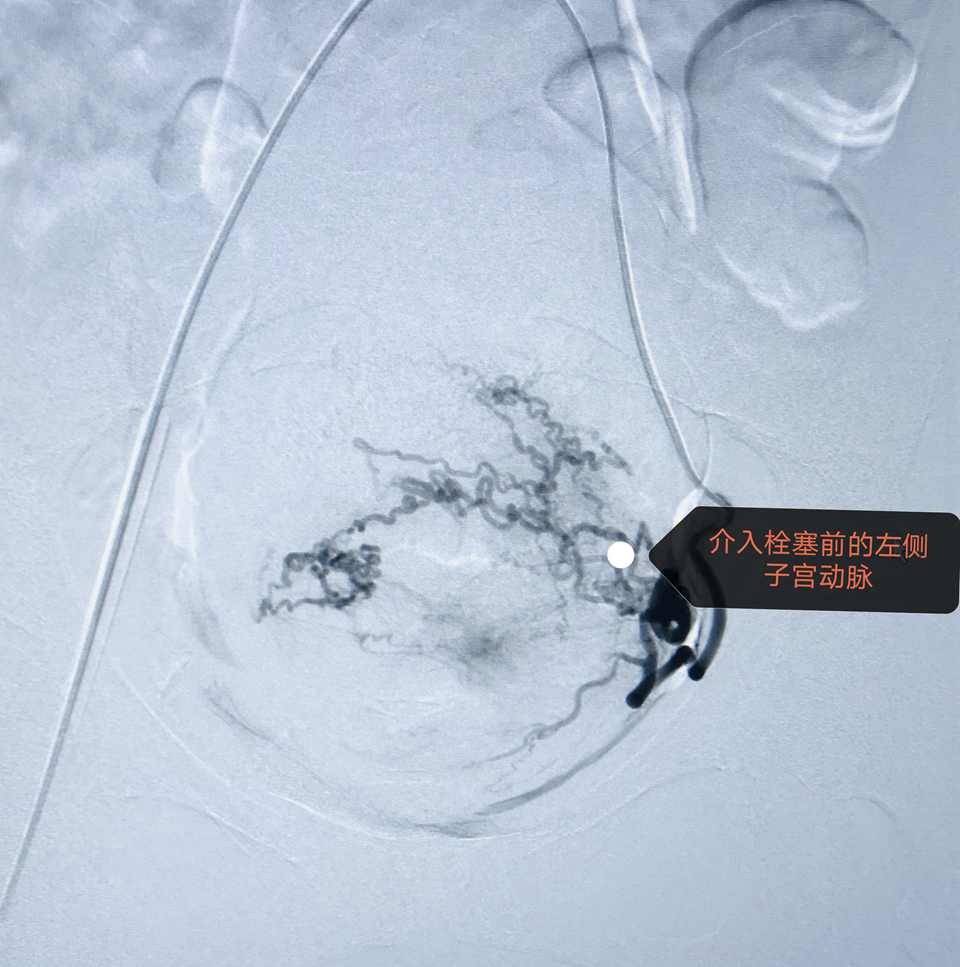

介入团队在局麻下行术前“腹主动脉球囊预置术”,球囊植入成功,产妇情况良好。随即在麻醉科配合下由产科手术团队行剖宫产术。当打开腹腔暴露子宫后,果断采用“阿氏”切口避开胎盘附着部位切开子宫,快速顺利取出胎儿。新生儿娩出后,探查宫腔证实胎盘覆盖整个子宫下段,为减少出血,介入团队及时充盈导管球囊、阻断流向宫体的血流。因胎盘粘连,快速徒手完整剥离。松开球囊,见胎盘创面渗血明显,且子宫收缩欠佳(按摩、强力宫缩剂已应用),子宫后壁广泛水泡状增生(内异症),为减少产后出血,迅速缝合子宫,遂行子宫动脉栓塞术。手术成功结束,术中出血量约500ml,跟一般剖宫产出血差不多,避免了输血及输血并发症的发生。术后母子情况恢复良好。